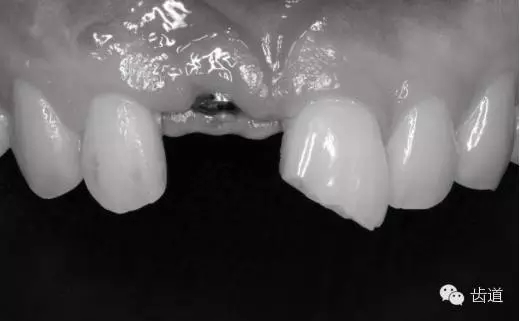

病例介紹 1.患 者: 黃某。性別:男。年齡:33歲 2.主 訴:上前牙外傷8個(gè)月。 3.現(xiàn)病史: 8個(gè)月前上前牙外傷,牙冠缺損,缺失。 缺失牙種植后, 轉(zhuǎn)診進(jìn)行樹缺損牙體的樹脂直接修復(fù)。否認(rèn)自發(fā)性疼痛和 夜間疼 痛。 4.既往史:無特殊。 5. 檢 查:11缺失,見種植體。21近中切1/3缺損,牙本質(zhì)不同程度暴露,無穿髓,探診敏感,冷刺激( +),叩診(-),無 松動(dòng),牙齦 無紅腫 。數(shù)字化X線攝影(DR)顯示:21近中切 角暗影至牙本質(zhì)中層,無穿髓。牙根連續(xù),無中斷,無牙周膜增寬,無根尖暗影。 6. 咬合檢查: 咬合無異常。無外傷后牙體移位導(dǎo)致的頜干擾。 7. 診 斷:11缺失,21冠折。 8. 治療計(jì)劃:21以腭側(cè)硅橡膠導(dǎo)板為依托序列化樹脂直接修復(fù)。后期如有更高美學(xué)要求進(jìn)行貼面修復(fù)或者全冠修復(fù) 。 9. 處 理 1). 間接和直接比色。 2). 取模,制作診斷蠟型,制作腭側(cè)硅橡膠導(dǎo)板。 3). 意大利美塑微混美學(xué)樹脂分層粘接直接修復(fù)。 4).顯微鏡下形態(tài)及表面紋理的精細(xì)修整和系統(tǒng)拋光。 5).定期復(fù)診。